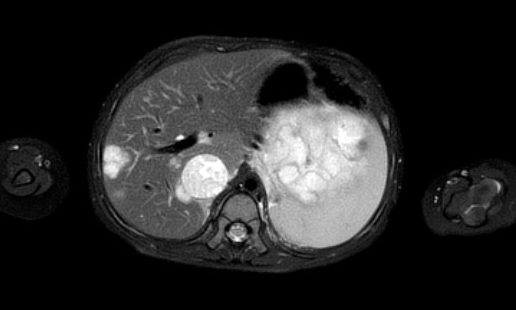

Hình ảnh

Hình ảnh MRI của một bé gái chín tháng tuổi có khối u ở bụng trái. MRI cho thấy khối u tuyến thượng thận trái, một phần đặc, một phần nang. Có nhiều di căn gan.

Khối u đã được sinh thiết. Có tình trạng chảy máu liên tục qua kim dẫn đường. Vào cuối thủ thuật, hai nút bọt gelatin đã được đặt vào (các dải tăng âm (mũi tên)).